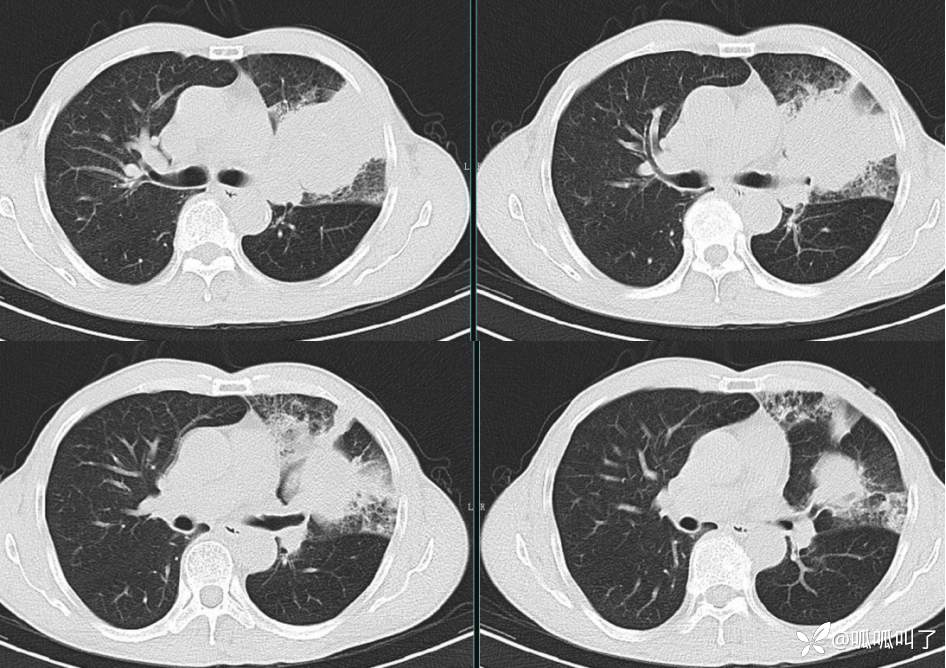

胸部CT平扫和增强: